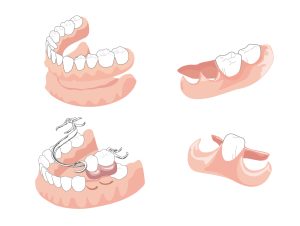

ブリッジや入れ歯と違い、周りの歯や組織に負荷をかけずに歯を作ることができるため非常に健康的で長持ちのする治療です。